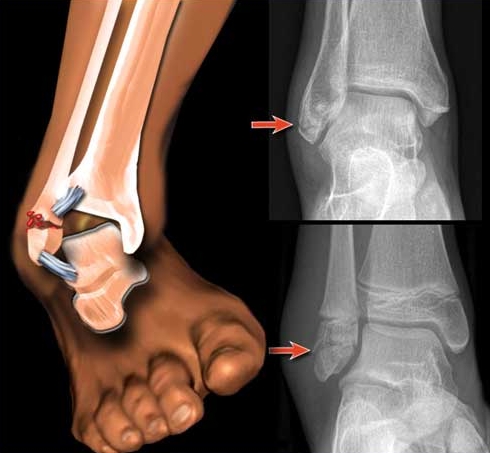

На изображении можно увидеть проявления остеопороза в области стопы. На ранних стадиях заболевание имеет очаговый характер, затрагивая не всю костную систему ступни, а лишь отдельные её элементы. При потере кальция костная ткань претерпевает серьезные структурные изменения. Плотность костей заметно снижается, теряется костная масса, и сами кости становятся тоньше. Это приводит к снижению их прочности.

В результате таких разрушительных процессов значительно увеличивается риск переломов поврежденной кости, даже при минимальных нагрузках.

Особенности прогрессирования остеопороза стопы заключаются в том, что заболевание может долго оставаться бессимптомным. Это затрудняет раннюю диагностику, и пациенты обращаются за помощью лишь тогда, когда повреждения костей становятся необратимыми. Главный признак патологии — повышенная хрупкость костной ткани. В таких условиях даже незначительные нагрузки могут привести к переломам в области голеностопного сустава. Резкие движения, приземление после прыжка или неправильное положение стопы при ходьбе могут спровоцировать травмы.